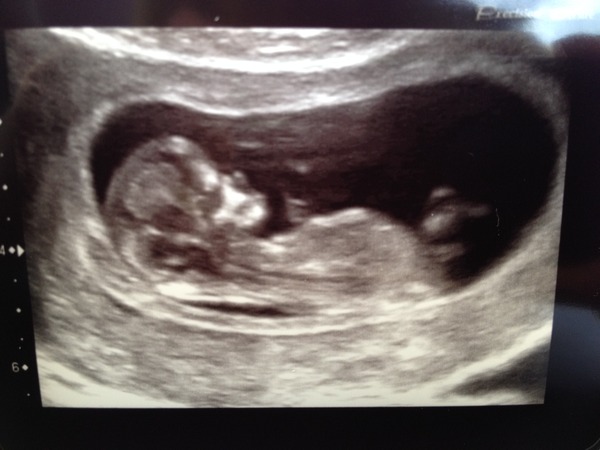

Our close family knew soon after we found out with all 3, it just felt right for us to tell them early on.